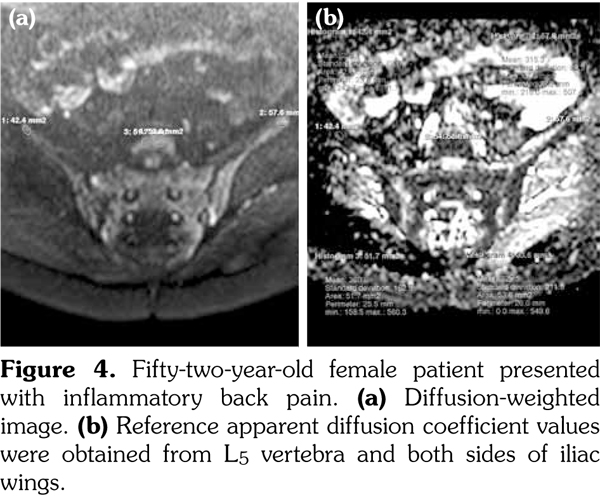

Sacroiliac joints were assessed according to ankylosing spondylitis criteria. Before evaluation of standard MRI protocol, patients’ information was removed from images. Afterwards, two experienced radiologists evaluated the images for the presence of inflammatory activity twice at separate sessions to assess interobserver variability. Following the examination of T2-weighted SPIR, contrast- enhanced T1-weighted SPIR, and DWIs at b values of 600 s/mm2, two radiologists and rheumatologists reached a consensus on the disease activity in the light of positive features of Berlin criteria. The DWIs were transferred to a separate workstation (Phillips, Extended MR workspace, 2.6.3.2.HF3, Netherlands). ADC maps were generated. T2-weighted SPIR images, contrast-enhanced images and diffusion-weighted images with ADC maps were put on the screen side by side. In the disease group, the hyperintense lesions on T2-weighted SPIR images and enhanced focuses on contrast- enhanced images were noted and the same lesions were marked on DWI images and ADC map. A circular ROI with a range of 40-75 mm2 was placed in those areas. In the control group a circular ROI was placed in the subarticular area of joints. Also, the same process was performed for the normal-appearing bone marrow areas near the joints of the disease group (Figure 2). Four standard measurements were conducted from each joint, including two on sacral and the other two on the iliac side for all patients (Figure 3). Additionally, two measurements were conducted from the fifth lumbar vertebra and one from each iliac wing (Figure 4). All measurements were performed twice. ADC values were expressed as square millimeters per second. The r-ADC ratio was calculated by dividing ADC value of subchondral bone or inflammatory lesions to ADC values of the fifth lumbar vertebra and iliac wings.

In the inflammatory back pain group, mean ADC measurements of all sacral and iliac bones were significantly higher than that of patients with mechanic back pain (Table 1). There was no significant difference between the mean ADC values of the bone marrow of L5 vertebra and iliac wings in patients with active sacroiliitis and mechanic back pain (Table 1). The mean ADC measurements of active lesions for both sides of joints for iliac and the sacral bones were significantly higher than either normal- appearing bone marrow areas in patients with active sacroiliitis or in patients with mechanical back pain (Table 1).

When the r-ADC ratios of both groups’ normal- appearing bone marrow and inflammatory lesions calculated by fifth lumbal vertebra were compared, r-ADC values of active lesions were considerably higher than normal-appearing bone marrow areas both in patients with active sacroiliitis or in patients with mechanical back pain. There was no significant difference between the r-ADC values of both groups’ normal-appearing subchondral bones calculated with L5 vertebra chosen as the reference organ (Table 1).

When the r-ADC ratios of both groups and inflammatory lesions calculated by iliac wing were compared, r-ADC values of active lesions were considerably higher than normal-appearing bone marrow areas both in patients with active sacroiliitis or in patients with mechanical back pain. Except from right iliac bone, there was no significant difference between the r-ADC values of both groups’ normal-appearing iliac and sacral bones calculated with iliac wings chosen as the reference organ (Table 1).